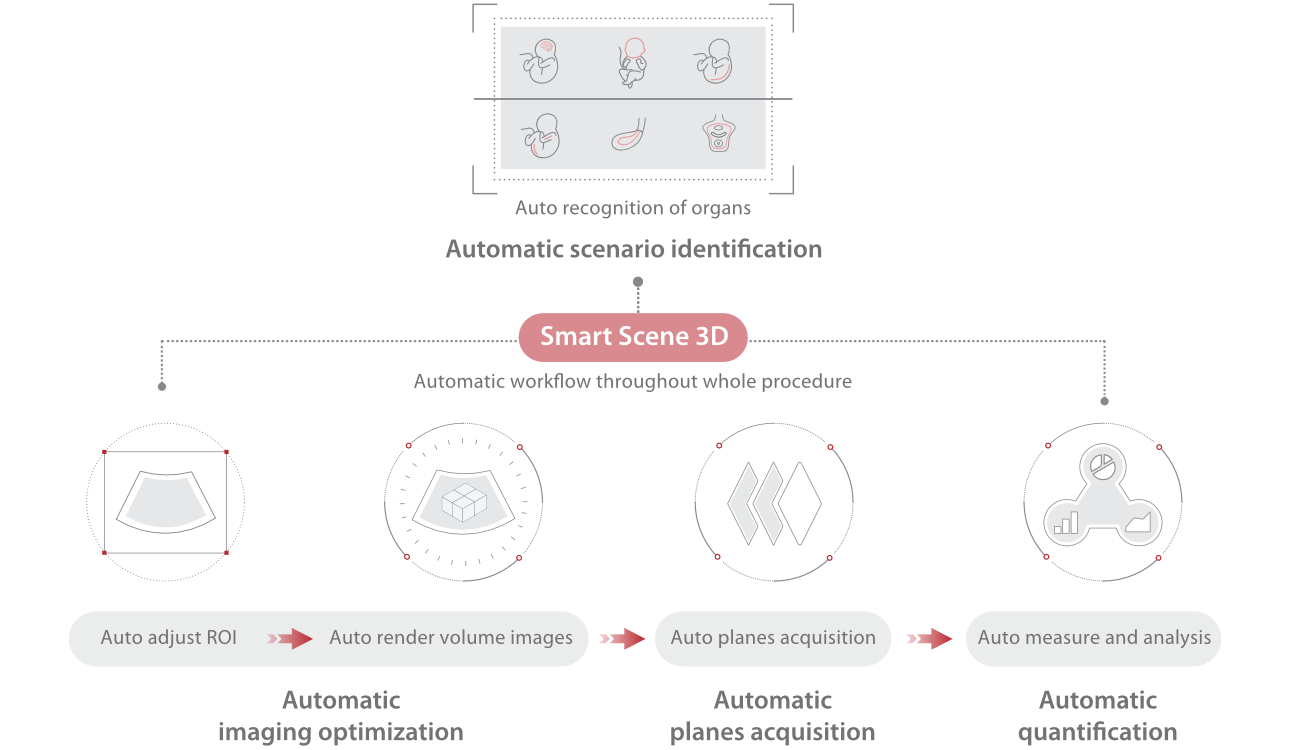

Nuewa I9, kad?nlara ve yenido?anlara y?nelik sa?l?k hizmetleri i?in ?zel olarak tasarlam??t?r ve i?ten d??a yenilik?i bir deneyim sunmaktad?r. Bu yenilikler, karma??k klinik senaryolara ili?kin derinlemesine bilgilere dayal? olarak geli?tirilmi?tir ayr?ca do?ru ve zaman?nda yan?tlar?n yan? s?ra, ola?an├╝st├╝ verimlilik ve ola?an├╝st├╝ kullan?c? deneyimi sunar.

ZST + Taraf?ndan Desteklenen Eksiksiz ??z├╝m

ZST+ platformu, ultrason evrimini temsil eden ola?an├╝st├╝ bir yeniliktir. Ultrason ?l?├╝mlerini geleneksel ???n bi?imlendirmeden kanal verilerine dayal? i?lemeye d?n├╝?t├╝r├╝r. Mekansal ??z├╝n├╝rl├╝k, zamansal ??z├╝n├╝rl├╝k ve doku homojenli?i aras?ndaki geleneksel dengeli s?n?rlaman?n ├╝stesinden gelir ve kesintisiz iyile?tirmelerle s?n?rs?z g?r├╝nt├╝leme ??z├╝mleri i?in ola?an├╝st├╝ g?r├╝nt├╝ kalitesi sunar.